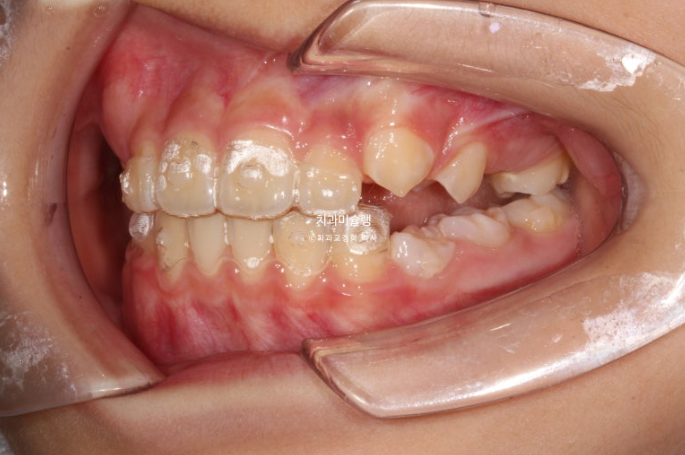

23년 10월 압구정 어린이 교정

교정치료를 위해 온 어린이 입니다.

23.10

윗니가 아랫니를 많이 덮어 아래 앞니가 안 보이는 과개교합이 있습니다.

중심선 불일치도 보입니다.

윗니 뻗침이 있어서 돌출을 느끼는 상태입니다.

앞니 위아래 4개씩 총 8개 영구치 앞니는 약간의 삐뚤함이 있지만 큰 공간부족 없이 잘 나온 편 입니다.

엑스레이 골격 분석 결과 아래턱이 작은 골격성 2급 부정교합 (소위 무턱)으로 진단되어 무턱치료도 하기로 합니다.

인비절라인 퍼스트의 Mandible advance 기능으로 못 자란 아래턱을 자라게 해줄 수 있습니다.